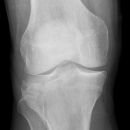

Kniegelenk